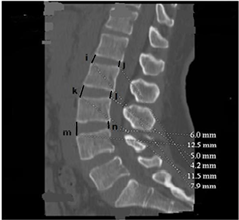

Figure 2. Mid sagittal section of the lumbar spine. i, k, m: heights of the anterior intersomatic space; j, l, n: heights of posterior intersomatic space; o, q, s: anterior heights of the vertebral bodies; p, r, t: posterior heights of the vertebral bodies.

1) The dimensions of the vertebral body (Figure 1 and Figure 2)

The anterior height increased from L1 to L5 and was significantly greater in men than in women (p < 0.001). Posterior height decreased from L1 to L5 and was significantly higher in men than in women (p < 0.001). The transverse and anteroposterior diameters increased significantly from L1 to L5 with mean values significantly lower in women than in men (p <0.001). These different dimensions are shown in Table 1.